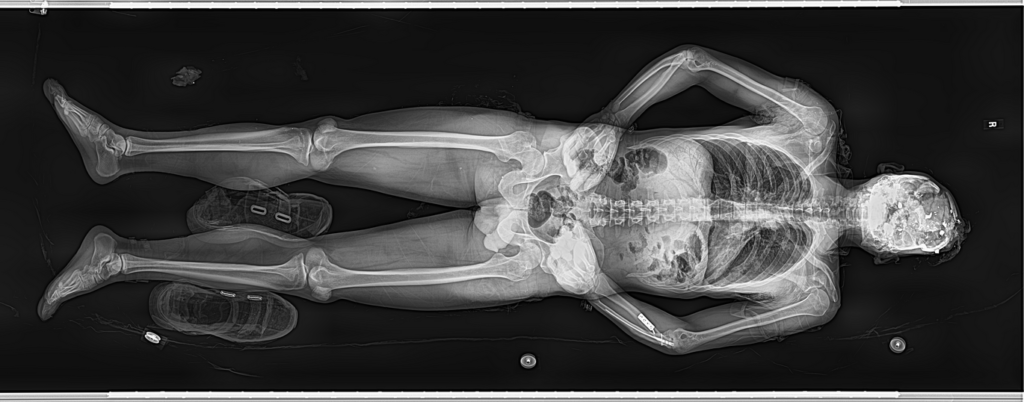

The Fobos XR machine is instrumental in dissecting the intricacies of traffic-related fatalities. It swiftly captures comprehensive body scans, highlighting internal injuries with remarkable clarity, thus enabling pathologists to ascertain death causes with heightened accuracy. These insights are critical for forensic inquiries.

Unprecedented in its scope, the Fobos XR’s scanning prowess is not limited to post-mortem analysis. Its expeditious and high-definition imaging capabilities extend to real-time, vital assessments of live patients, thereby becoming instrumental in emergency situations.

It enables rapid and precise visualization of internal trauma, guiding urgent surgical interventions, and shaping crucial clinical decisions.